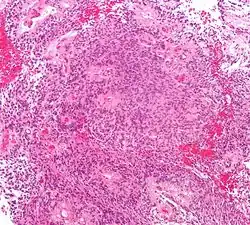

Ependymomas are composed of cells with regular, round to oval nuclei. There is a variably dense fibrillary background. Tumor cells may form gland-like round or elongated structures that resemble the embryologic ependymal canal, with long, delicate processes extending into the lumen; more frequently present are perivascular pseudorosettes in which tumor cells are arranged around vessels with an intervening zone consisting of thin ependymal processes directed toward the wall of the vessel.[5]

-

Micrograph of a myxopapillary ependymoma. HPS stain. -